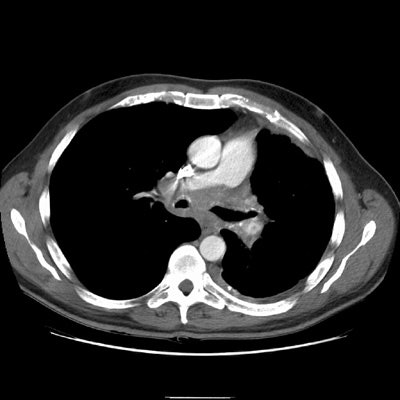

Again note abnormality involving the left pulmonary artery and airway narrowing.